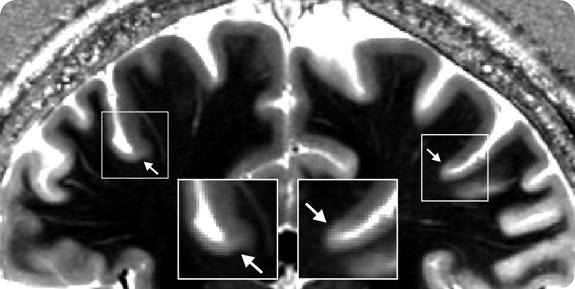

Picture: High-field MR image of a 25 year old human subject’s brain (field strength 7 Tesla, spatial resolution: 0.6mm). The arrow marks a drop in contrast at the base of the precentral gyrus. The border matches the corresponding border between the primary motor (Brodmann area 4) and somatosensory (Brodmann area 3a) cortex.

A new generation of MRI scanners with ultra-high field strength and a possible resolution of under 0.5mm can now solve this problem. Using their ultra-high field 7Tesla MRI scanner, researchers from the Department of Neurophysics succeeded in making the functionally important border between primary motor and somatosensory cortex much more clearly visible in the brains of living volunteers. This achievement opens up a completely new approach in the direction of an individually specific map of the cortex. It is also a first step towards making direct comparisons between microstructure and function in the living human brain possible.